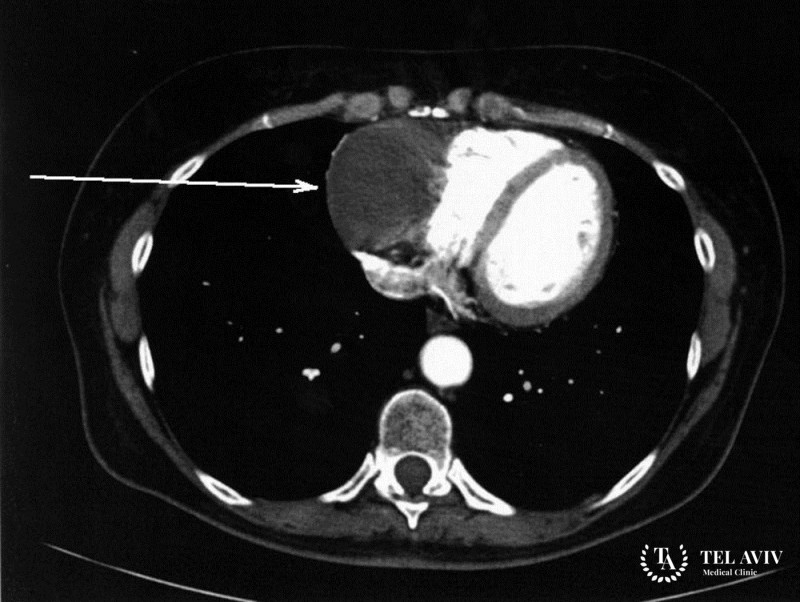

Параганглиома сердца – представляет собой новообразование симпатической и парасимпатической нервной системы. Заболевание встречается крайне редко и развивается бессимптомно. Зачастую врач может обнаружить патологию в предсердии или межсердечной перегородке. Симптоматика заболевания похожа на проявление других недугов. С этим связано позднее обращение пациентов за квалифицированной помощью. Опытный врач может обнаружить случайно. во время проведения диагностики по другому вопросу.

- КТ или МРТ;